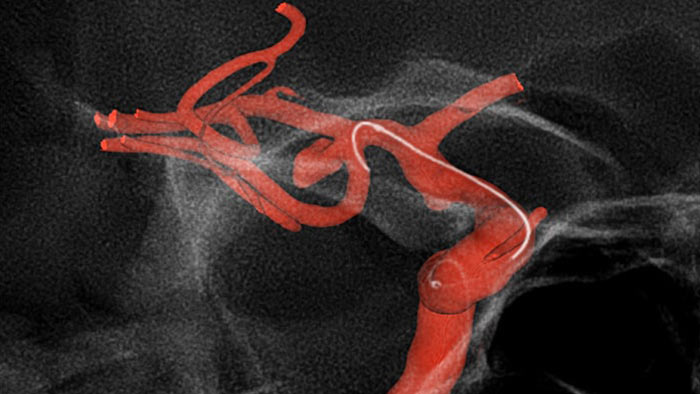

Используйте полученные ранее данные КТ- или МРТ-ангиографии и совмещайте их с данными рентгеноскопии в режиме реального времени, чтобы визуализировать границы поражения и соответствующей васкуляризации для оценки рисков. Повторное использование полученных ранее данных помогает контролировать дозу облучения и количество контрастного вещества.